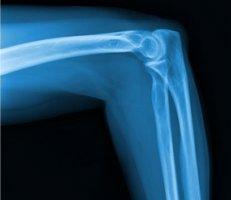

Your specialist may be able to determine if your elbow and arm pain are due to tennis elbow after a review of your symptoms and a physical examination of your arm and elbow. In some cases, diagnostic imaging, such as an MRI or X-ray, may be needed to rule out other causes of your pain.